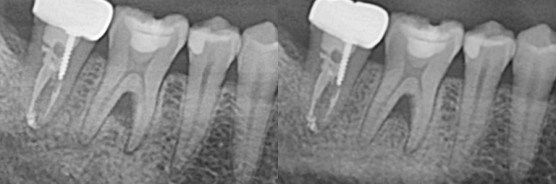

[2022.01.04 염증은 사라지고 뼈가 찬 모습]

뿌리 끝, 그리고 뿌리 사이에 있던 염증이 안보이죠?

치아에 대한 증상은 말끔하게 없어졌고 오히려 뼈가 잘 차오른 모습을 보여주고 있습니다.

[신경치료 전/후 비교사진]